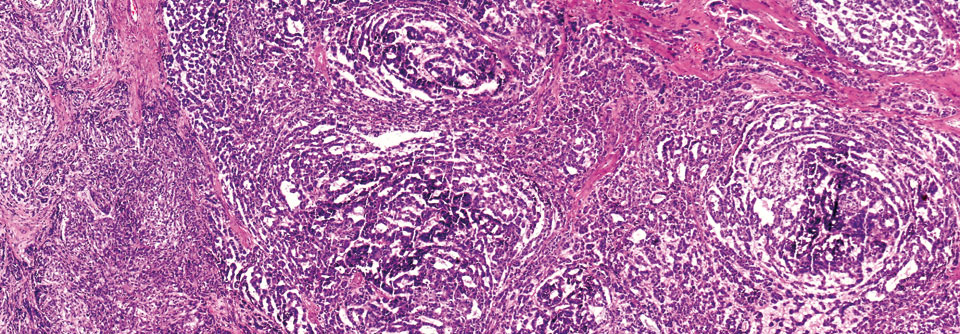

Das Analkarzinom ist eine bösartige Geschwulst am After. Liegt der Tumor zwischen der Linea dentata und der Linea anocutanea, spricht man von einem Analkanalkarzinom. Davon abzugrenzen sind die Analrandkarzinome an der Haut-Schleimhaut-Grenze.